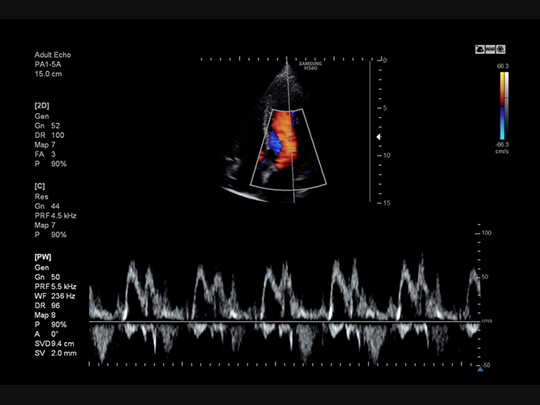

S-Flow™

A sophisticated color Doppler technology with greater sensitivity, S-Flow can detect low-intensity blood flow. It enables accurate diagnosis when blood flow examination is especially difficult.

Phased array transducers

PA1-5A

- Application: abdomen, cardiac, vascular